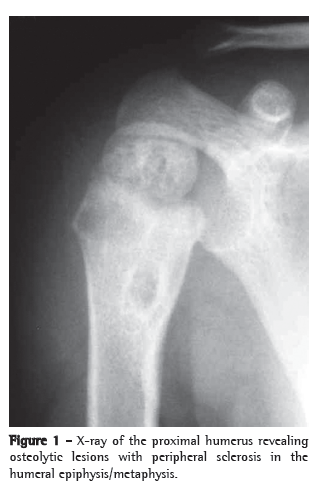

A 21-month-old boy, born in São Paulo, presented with fever and mild functional impairment of the right upper limb. The child had daily episodes of fever (> 38°C), predominantly at night. One week prior, the child had started presenting pain upon palpation and upon movement, as well as limited movement of the right arm. The mother stated that the boy had no history of local trauma. An X-ray of the right upper limb revealed a lytic lesion of the proximal epiphysis/metaphysis, with ill-defined borders, surrounded by a halo of reactive bone sclerosis, periosteal reaction and soft tissue edema (Figure 1). Magnetic resonance imaging revealed areas of abnormal marrow signal and soft tissue edema with highlighting of the infected marrow by the contrast medium-signs consistent with osteomyelitis of the proximal humerus (Figure 2). The patient received cephalosporin for 10 days in an outpatient setting. On day 8 of the antibiotic therapy, the child came to our facility due to fever and persistent pain.

On X-rays, lytic lesions with a sclerotic halo can be seen, as can periosteal reaction and periarticular osteoporosis.(4,9-11) Histopathological studies show granulomatous inflammation with epithelioid cells, with or without caseous necrosis. Acid-fast bacilli are detected in approximately half of all cases, and most present strongly positive PPD reactions.(9,12)

Lytic and sclerotic bone lesions with periosteal reaction characterize the radiographic lesions. In the case described here, the CT findings in the epiphysis, the metaphysis and the diaphysis were consistent with previous descriptions in young patients. Older children usually present only metaphyseal changes.(4)